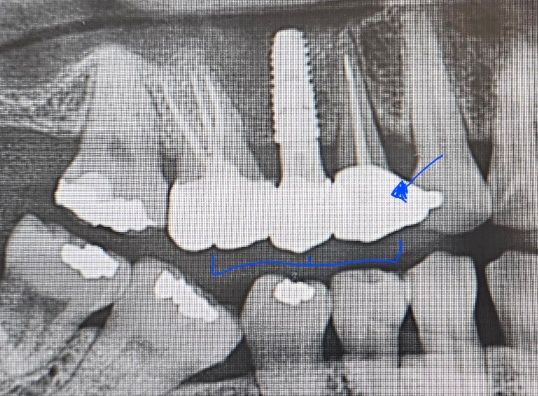

세개한 이빨이고 화살표 치아가 아파요ㅜ

크라운 두개 임플란트 같이해서 크라운 완료-2023.11월쯤

선생님께서 좀 더 갈아(?)주시고 다시 사용해보기로 했는데 지금 이빨 딱딱딱 하면 쬐금 아픕니다ㅜ